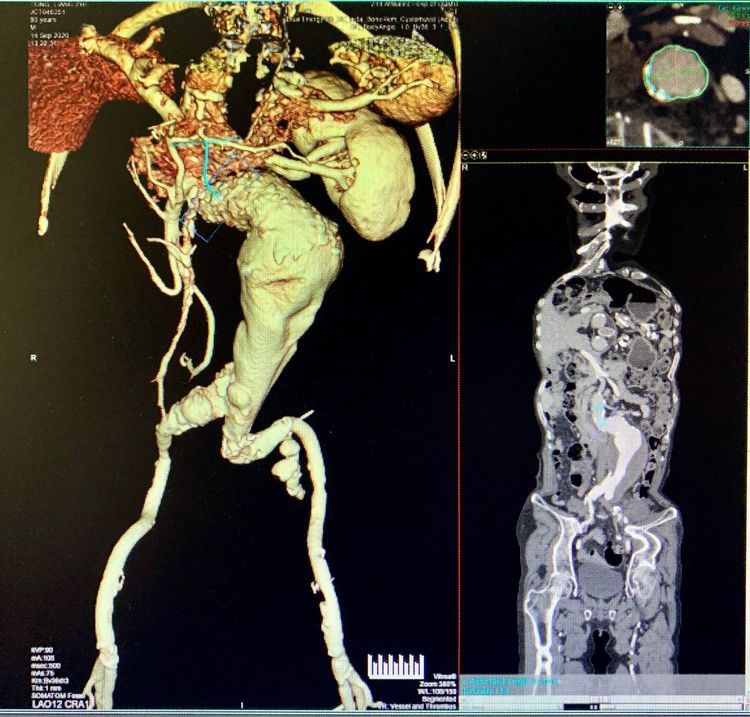

1.此病例腹主动脉扭曲严重,瘤颈成角90度,不符合报道的解剖标准:瘤颈长度≥10 mm、瘤颈成角≤75度。

2.双侧髂动脉扭曲,左侧严重,属于困难入路。

3.腹主动脉瘤体较大,远端管腔内腹壁血栓较多。髂腿选择非常困难,也存在术中血栓脱落致下肢动脉栓塞风险。

4.右肾动脉闭塞,右肾未显影。术后肾功能衰竭风险较高。

使用全穿刺技术(Preclose技术),建立双侧股动脉及右侧肱动脉入路。“全身像”显示:瘤颈成角约90度,左侧髂总动脉钙化扭曲严重,双侧髂内动脉显影,左侧髂内动脉瘤。